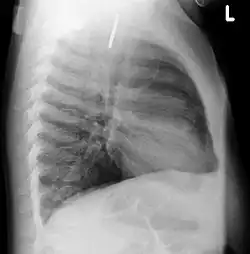

Инородные тела ЖКТ

(слева — в прямой, справа в боковой проекции) — видно инородное тело (монета) пищевода.

Одна из распространённых локализаций инородных тел — желудочно-кишечный тракт. Возможные пути проникновения инородных тел — ротовая полость[13] или прямая кишка[14]. Дети чаще проглатывают монеты[15], у взрослых в 75% случаев инородными телами служили мясные кости[16].

Наиболее часто проглоченные предметы обнаруживают в пищеводе или желудке, реже в глотке или двенадцатиперстной кишке[17].